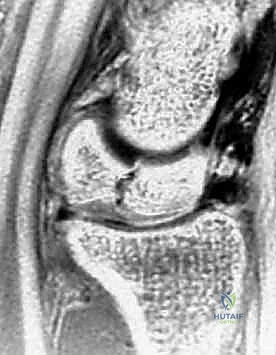

- الأشعة السينية (X-rays): هي الخطوة الأولى. في المراحل المبكرة جداً، قد تظهر الأشعة السينية طبيعية تماماً. في المراحل اللاحقة، يظهر العظم الهلالي بلون أبيض ناصع (متصلب)، ثم يبدأ في الظهور مفلطحاً أو متفتتاً.

- التصوير بالرنين المغناطيسي (MRI): هو المعيار الذهبي للتشخيص المبكر. يمكن للرنين المغناطيسي اكتشاف نقص التروية الدموية (وذمة العظم) قبل أشهر من ظهور أي تغيرات في الأشعة السينية. يعتمد الدكتور هطيف بشكل كبير على الرنين المغناطيسي لتحديد مرحلة المرض بدقة.

- التصوير المقطعي المحوسب (CT Scan): يُستخدم لتقييم مدى تفتت العظم الهلالي وبنيته ثلاثية الأبعاد، وهو أمر حاسم في التخطيط الجراحي.

مراحل ليختمان (Lichtman Classification) لمرض كينبوك

يُصنف المرض عالمياً باستخدام نظام ليختمان، وهو دليل أساسي يحدد مسار العلاج:

| المرحلة الأولى (Stage I) | أشعة سينية طبيعية. ألم خفيف. الرنين المغناطيسي يظهر نقص التروية. العظم محتفظ بشكله. | علاج تحفظي (تثبيت) أو تدخل جراحي بسيط لتحسين التروية. |

| المرحلة الثانية (Stage II) | الأشعة السينية تظهر العظم الهلالي أكثر بياضاً (تصلب). العظم لا يزال محتفظاً بشكله العام ولكن قد تظهر خطوط كسر دقيقة. | جراحة لتفريغ الضغط أو زراعة طعم وعائي. |

| المرحلة الثالثة أ (Stage IIIA) | انهيار وتفلطح العظم الهلالي. تفتت الأجزاء. لا يوجد انهيار في ارتفاع عظام الرسغ الكلية. | زراعة طعم عظمي وعائي + جراحة تسوية المفصل (تقصير العظم الكبير أو تطويل الكعبرة). |

| المرحلة الثالثة ب (Stage IIIB) | انهيار العظم الهلالي مع انهيار ارتفاع الرسغ وانحراف العظم الزورقي. ميكانيكا الرسغ مضطربة. | دمج جزئي لعظام الرسغ (Partial Wrist Arthrodesis) أو استئصال الصف القريب. |

| المرحلة الرابعة (Stage IV) | انهيار كامل للرسغ مع تطور خشونة متقدمة (التهاب مفاصل) في المفاصل المجاورة. | دمج كلي للرسغ (Total Wrist Arthrodesis) أو استبدال المفصل. |